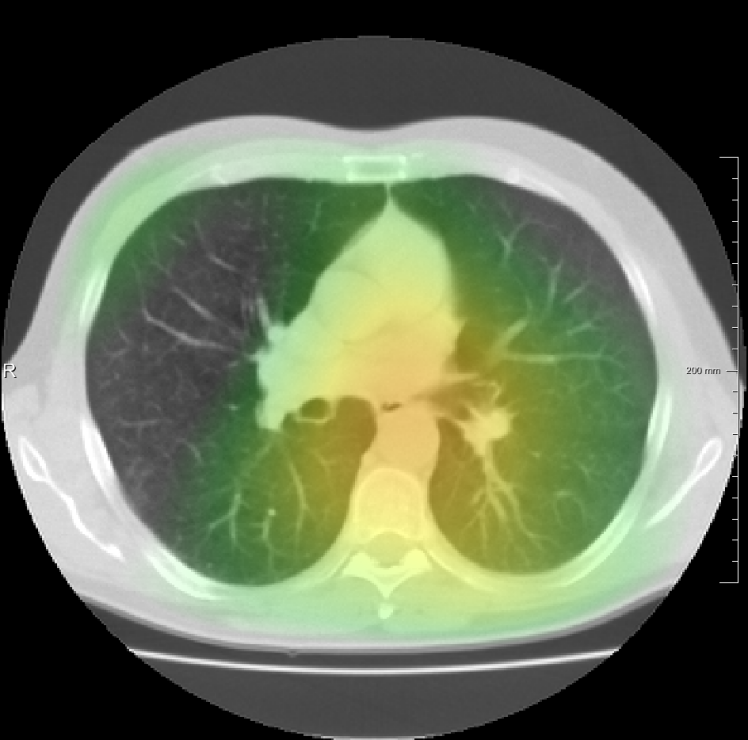

In total we generate 14 basis types of artificial DVFs: 5 single frequency, 4 mixed frequency, 4 respiratory motion and 1 identity. The precise settings of the parameters are available in Table I and examples are given in Fig. 4. The histograms of the Jacobians are also available in this figure. When the spatial frequency is increased, the Jacobian histograms will spread more, which shows that local relative volume changes are increased. The value of , the maximum artificial displacement along each axis, is chosen as 20, 15 and 7 for RegNet4, RegNet2 and RegNet1, respectively.

For the DIR-Lab-4DCT database, a comparison between RegNet and affine, B-spline (three resolutions), an advanced conventional registration method using sliding motion (Berendsen et al., 2014) and three other CNN-based methods (Eppenhof and Pluim, 2018; de Vos et al., 2019; Sentker et al., 2018) is available in Table IV. It can be seen that training with “S+M” improved performance slightly with respect to just “S”. Adding the respiratory motion category improved performance substantially, as these are inhale-exhale pairs; this is predominantly caused by the patients where the TRE after affine registration was still quite large. An example visualization is also available in Fig. 5(f), showing that adding the respiratory motion category can align images better in the diaphragm region. The advanced conventional registration method that leverages sliding motion (Berendsen et al., 2014) is still better than RegNet. Note that RegNet was not trained on the DIR-Lab-4DCT data, similar to Eppenhof and Pluim (2018); Sentker et al. (2018). However, de Vos et al. (2019) and Eppenhof and Pluim (2018)-DIR methods were trained on the same database but using cross-validation to report the results. Also note that the results reported in Sentker et al. (2018) are averaged over all phases of DIR-Lab-4DCT (T00 to T10), while the results of other CNN methods (including RegNet) are reported between the maximum inhale and maximum exhale phase (T00 and T50). These reported results are therefore likely somewhat better than the results for T00 and T50 only.